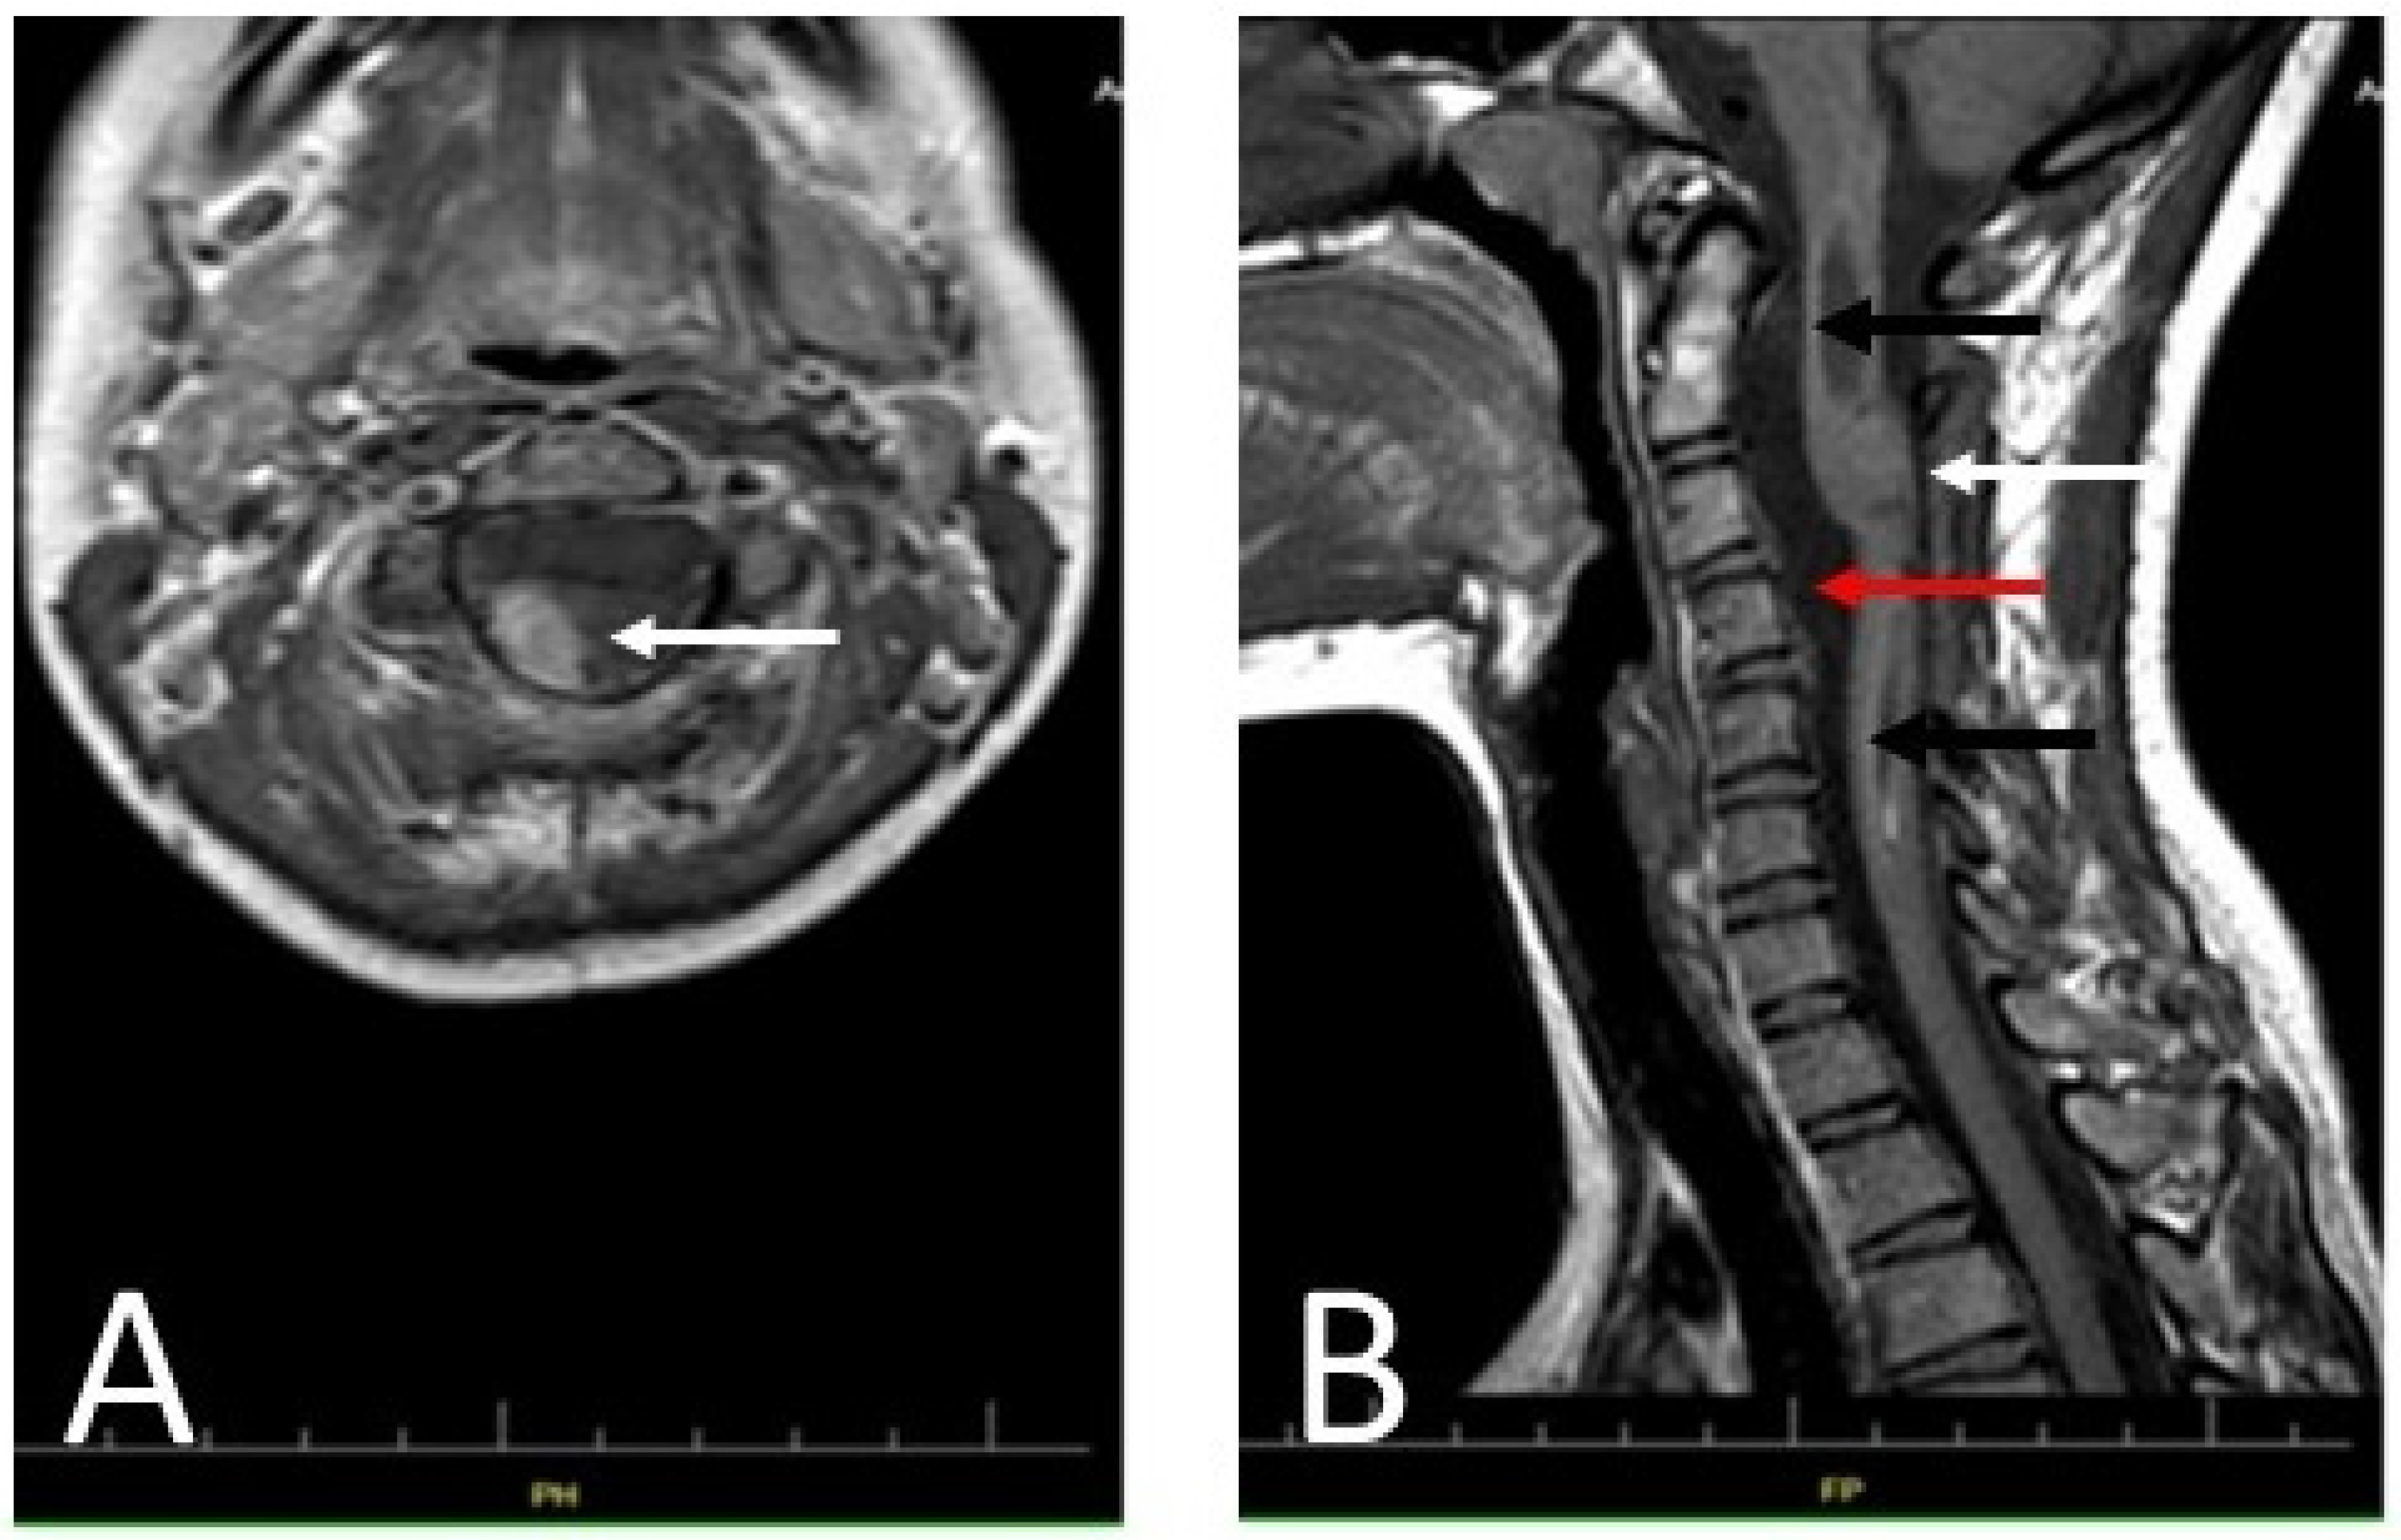

Additionally, an MRI of the cervical spine was performed (Figure 6). The remaining part of the cervical spine tumor, not resected during the previous surgery, showed no changes compared to the former MRI examination.

Figure 6.

Diagnostic T1-weighted MRI images of the patient’s cervical spine: (A) An axial section at the C2 level of the patient’s cervical spine made after administration of a contrast agent. The remainder of the tumor showed no apparent progression compared to the MRI performed 48 h after the first treatment (arrow). (B) A sagittal section of the patient’s cervical spine (without contrast). The photo shows decompression of the syringomyelic cavity (black arrows) and the remains of the partially removed tumor, visible as an isointense lesion in the spine (white arrow). The reserve of cerebrospinal fluid in the spinal canal is clearly increased (red arrow). The photo shows no signs of tumor progression.